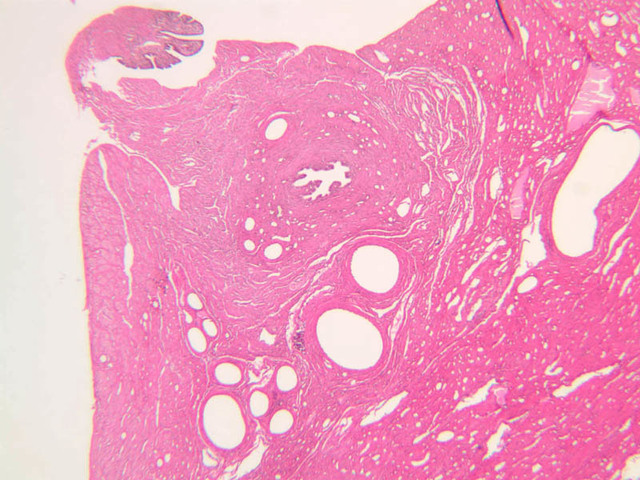

The resting or inactive mammary gland consists of predominantly dense connective tissue with small clusters of ducts and a few glandular elements (slide A-93 [2.5x-labeled, 10x, 20x, 40x] [1x, 2.5x, 10x, 20x]). It is difficult to differentiate between small ducts and alveoli as each is lined by simple low cuboidal cells. Lobes and lobules are not well defined. During puberty, predominantly under the influence of the ovarian hormone estrogen, the glandular or epithelial ducts proliferate and begin to differentiate into clusters of ductal and alveolar units termed terminal ductal lobule units (TDLUs). The non-pregnant gland will form multiple TDLUs that will not fully differentiate until pregnancy-induced growth. TDLUs are classified into Type I, Type II and Type III based on density of the ductules within each lobular unit. Type I and Type II lobules are typical of inactive glands that have not undergone a pregnancy cycle. Type III lobules are seen only in active glands or in inactive glands that have been through a pregnancy. Intralobular connective tissue is loose connective tissue that surrounds the alveoli and ducts within a lobule. The interlobular connective tissue is dense and contains considerable adipose tissue.

During pregnancy, predominantly under the influence of the ovarian hormone progesterone and the pituitary hormone prolactin, the glandular elements proliferate and differentiate to form milk-secreting units. In later stages of pregnancy, alveolar development becomes prominent and the amount of connective tissue and adipose tissue decreases. The secretory cells hypertrophy and accumulate secretory product.